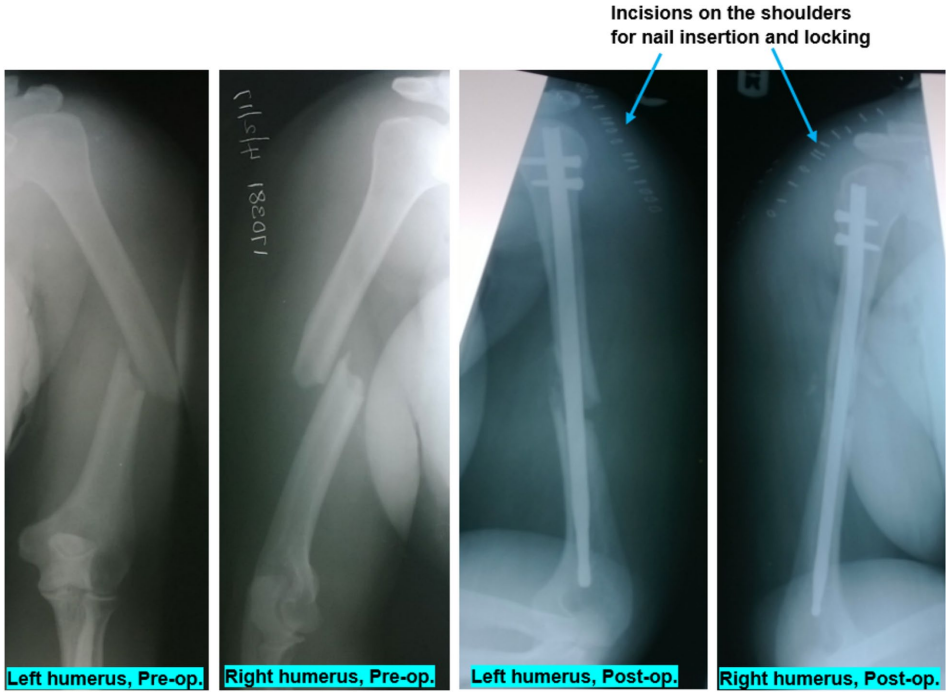

尼日利亚鲍文大学教学医院的研究团队在《Journal of Medical Case Reports》发表了一项突破性病例研究。该团队收治了一名43岁健康女性患者,其在未系安全带的小型客车侧翻事故中,因特殊受力机制导致双侧肱骨中段AO/OTA 12A2型骨折,损伤严重度评分(ISS)仅为10。研究采用无透视条件下的SIGN Fin髓内钉技术,通过单一手术同时固定双侧骨折,实现了术后7天出院、12周影像学愈合的优异疗效,并完成长达7年的功能随访。

研究团队在伤后第4天实施同期双侧手术,采用SIGN Fracture Care International捐赠的Fin钉系统。该技术通过肩峰端小切口置入鳍状髓内钉,既避免传统锁钉的射线依赖,又减少手术时间和出血量。如图1所示,Fin钉的独特设计通过骨管内鳍状结构实现稳定性,较标准钉减少30%手术时间。

术后影像学显示双侧骨折线对位良好(图2)。随访数据显示:6周开始骨痂形成,12周达到三皮质愈合标准;UCLA评分从术后17分提升至35分满分;7年随访证实患者完全恢复家务和教学工作能力。